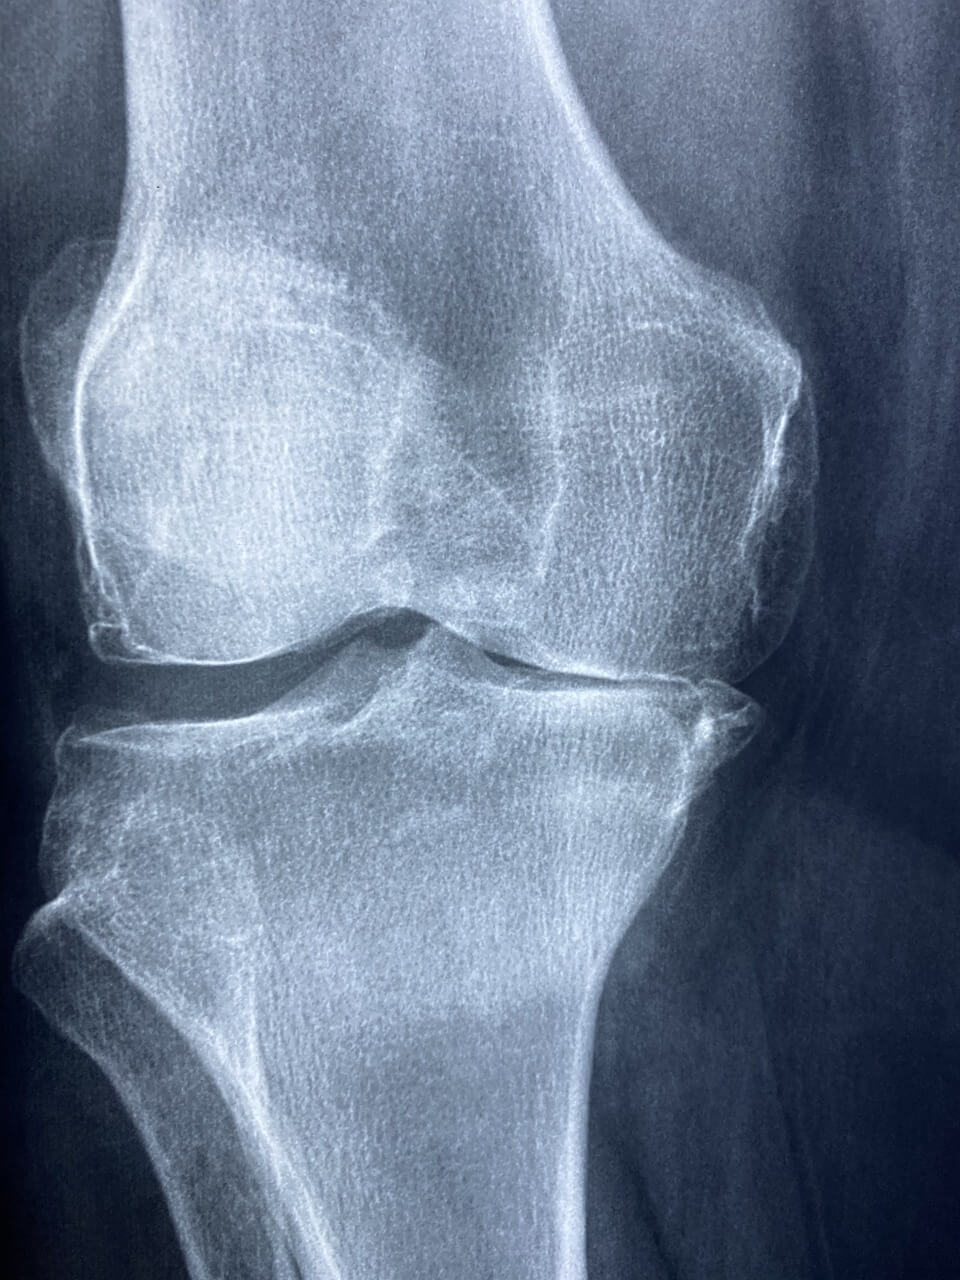

척추 협착증은 흔히 등과 허리 부위에서 발생하는 통증으로, 디스크의 변형, 골수나 신경 조직의 압박 등으로 인해 발생합니다. 이로 인해 통증, 저림 혹은 약해진 근육 등의 증상이 나타납니다. 또한, 증상은 시간이 지남에 따라 점차 악화될 수 있으며, 척추 협착증으로 인한 통증은 일상 생활에 큰 영향을 미치는 경우가 많습니다. 통증이 심해질수록 일상생활에 제약이 생기기 때문에 빠른 해결이 필요하며, 정확한 원인 파악을 위해 신속하게 전문가와 상담 받으시는 편이 좋습니다.

척추 협착증의 원인은 다양한데, 주로 나이가 들면서 디스크가 변형되거나 척추 관절의 변화, 골수의 종양, 척추 관절염 등이 원인이 될 수 있습니다. 또한 외상이나 척추 관련 질환으로 인해 발생할 수도 있습니다. 척추 협착증은 일상생활에 큰 영향을 미치기 때문에 원인을 파악하고 조기에 치료를 받는 것이 중요합니다. 따라서, 정확한 원인을 파악하고 적절한 치료를 받기 위해 전문가와의 상담이 필요합니다.